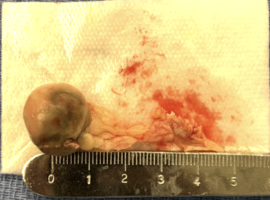

Clinical Cardiology Case Report

The Journal offers case reports in clinical cardiology, images, case series and heart surgery videos to publish. original research, research articles, review articles, case studies, commentaries, short communication, and Letters to the heart problem, heart and blood vessel disorders, cardiovascular diseases, myocardial infarction (heart attack), issues of cardiac arrest, stroke, techniques and procedure used in stent implantation, anticoagulant drugs (blood thinners), basic research in heart structure and functions and other medical conditions and associated treatments is aiming to stand out and publish remarkable findings in the major areas of cardiovascular medicine emphasizing on diagnostic, therapeutic and disease management sections.